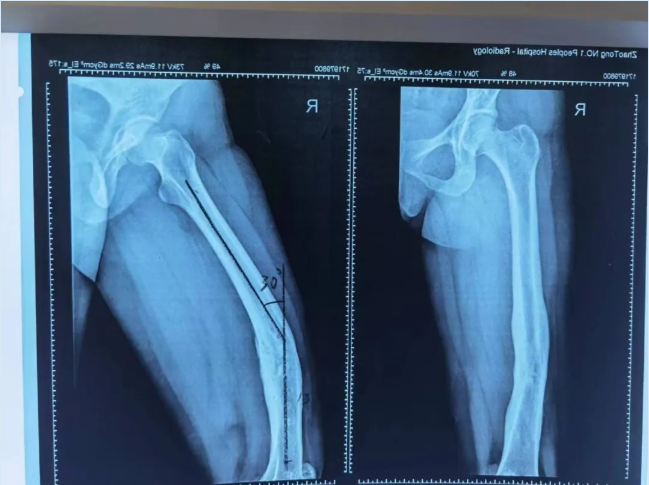

经接诊医师崔家平检查发现,患者右股骨畸形并功能障碍,右膝关节僵硬,不能活动;影像检查后发现右下肢前后及内外成角畸形明显,测量发现右侧股骨前后成角30度,内外成角19度,患者及家属急盼迅速治疗以缓解疼痛、矫正畸形。

(术前检查影像)